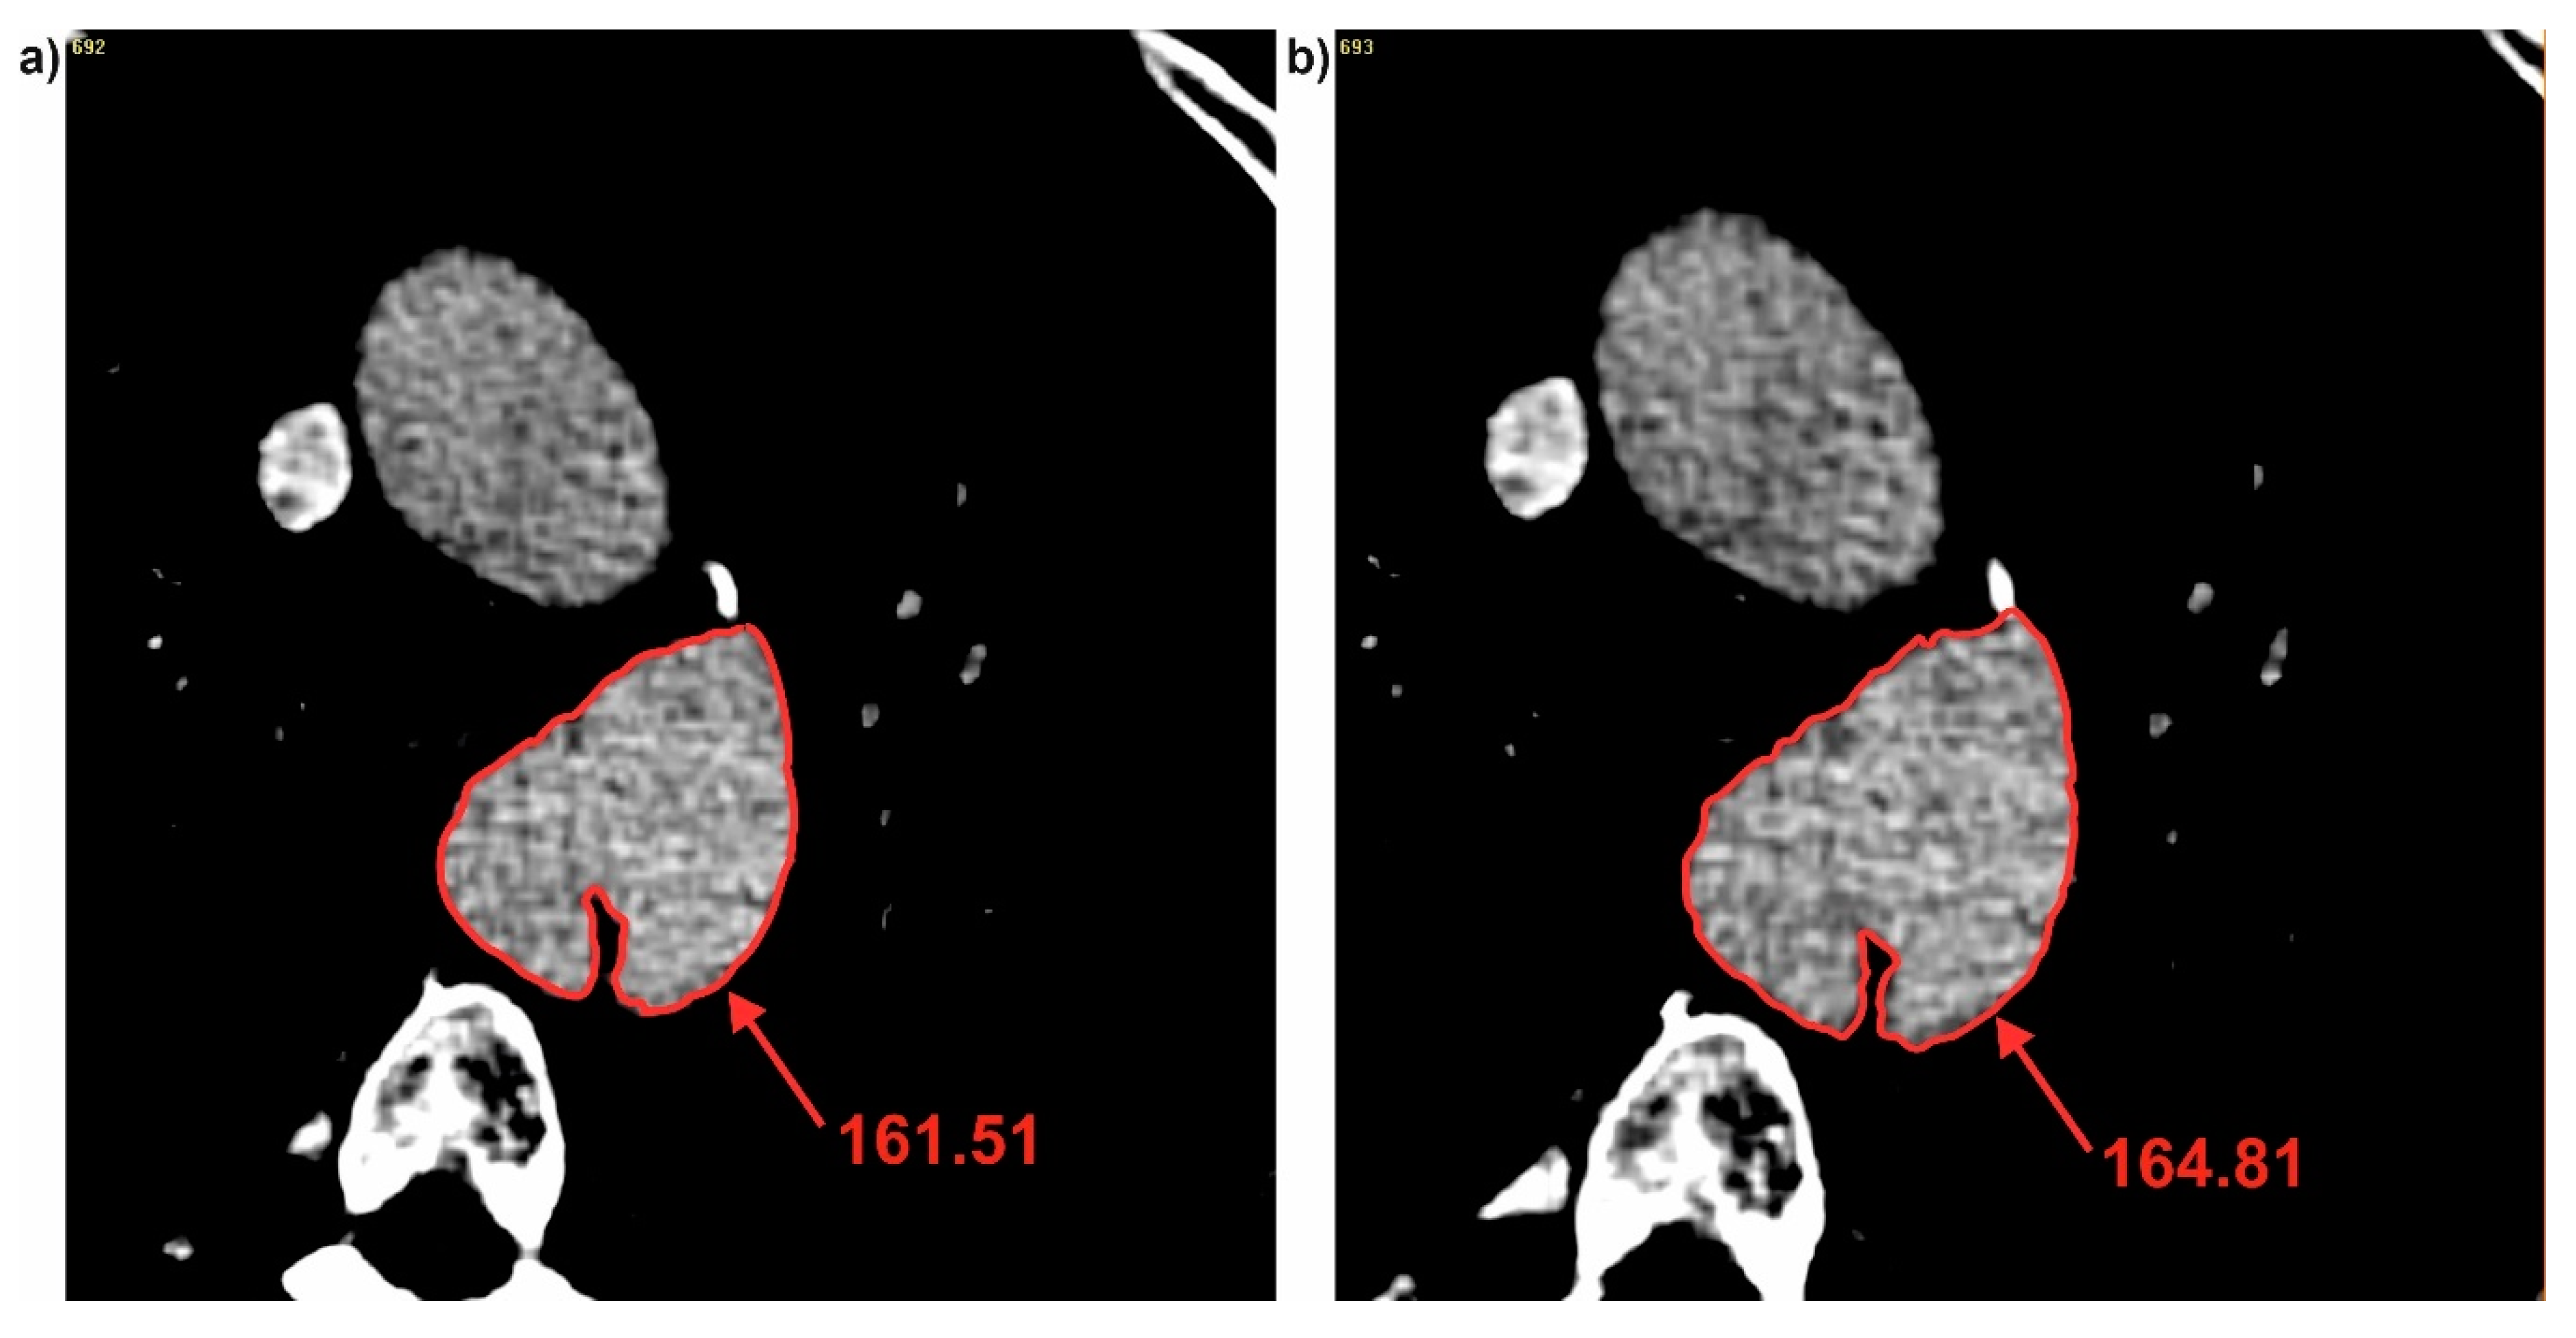

Next, brightness value for each cross-section for all three patients was analyzed. It was observed that with decrease of diameter, brightness value increased for the common duct for both DF and DHy (Figure 5). For P1 decrease of diameter was from 49.27 to 47.37 (calculated for DF) and from 43.62 to 43.08 (calculated for DHy) indicating an increase of brightness value from 161.51 to 164.81 for the common duct (for cross-section 3 and 4) (Figure 6). Similar trend was observed for the true and false ducts. Decrease of diameter for P1 for the false duct was from 26.65 to 20.80 (calculated for DF) and from 19.35 to 17.99 (calculated for DHy) indicating an increase of brightness value from 156.88 to 161.07 (for cross-section 11 and 12) (Figure 7a). While for the false duct a decrease of diameter for P1 was from 32.70 to 35.78 (calculated for DF) from 33.16 to 36.50 (calculated for DHy) indicating an increase of brightness value from 177.06 to 173.21 (for cross-section 11 and 12) (Figure 7b).

Figure 6. Brightness of common duct for P1: (a) Cross-section number 3 and (b) cross-section number 4. Values of brightness were calculated in Pixels.